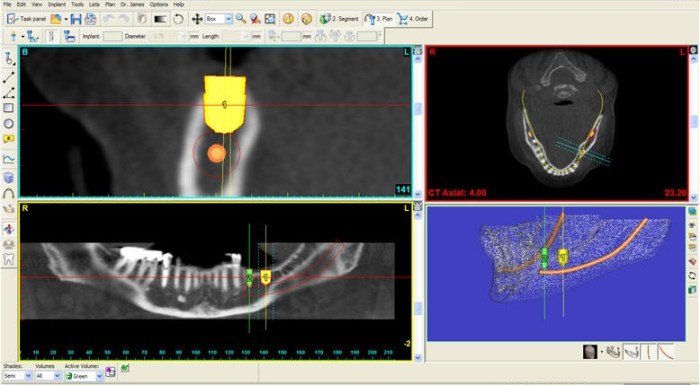

Bước 2: Chụp phim kiểm tra cấu trúc xương

Nha Khoa Á Đông được trang bị các thiết bị hiện đại giúp bác sĩ nắm rõ được cấu trúc xương hàm và hệ thống dây thần kinh. Nhờ vào số liệu thu nhập được bác sĩ sẽ biết được tình trạng xương hàm có đủ để cấy ghép implant không và nên áp dụng loại nào là là phù hợp.

Bước 3: Sử dụng phần mềm simplant giả định các vị trí cấy ghép implant

Từ số liệu thu được ở bước 2, bác sĩ Nha Khoa Á Đông sẽ sử dụng phần mềm simplant để mô phỏng vị trí cấy ghép implant trên không gian 3 chiều. Nhờ vào phần mềm này bạn có thể hình dung ra quá trình cấy ghép implant của mình và thống nhất với bác sĩ kế hoạch điều trị để có được kết quả phục hình như mong muốn.